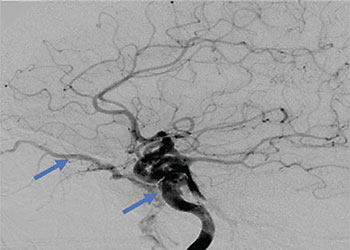

Endovascular:

Carotid Cavernous Fistula (CCF) Study

Author: Jonathan L. Brisman M.D., F.A.C.S., Read More!